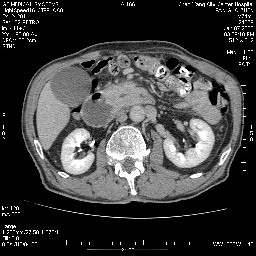

女,74岁,呕吐10余日

壶腹部的占位性病变,考虑为十二指肠癌并梗阻,但脾内多发性低密度区为转移吗?

还有胃、脾之间可见有侧支循环建立。左肾盂积水。

考虑来源于十二指肠水平段的恶性占位,侵及周围组织,特别是胰腺,可见区域淋巴结肿大,左侧下腔静脉畸形。

双肾多发小囊肿;左肾积水。

十二指肠水平段腔内占位伴梗阻,中等度较为均匀的强化,洗脱慢,区域淋巴结显示增多,符合腺癌表现。下腔静脉变异。

支持十二指肠腺癌伴梗阻.,下腔静脉发育变异.

十二指肠水平部腺癌伴梗阻并侵犯邻近结构。下腔静脉发育变异。

今日手术结果:胰腺钩突癌侵犯十二直肠,腹腔淋巴结转移.